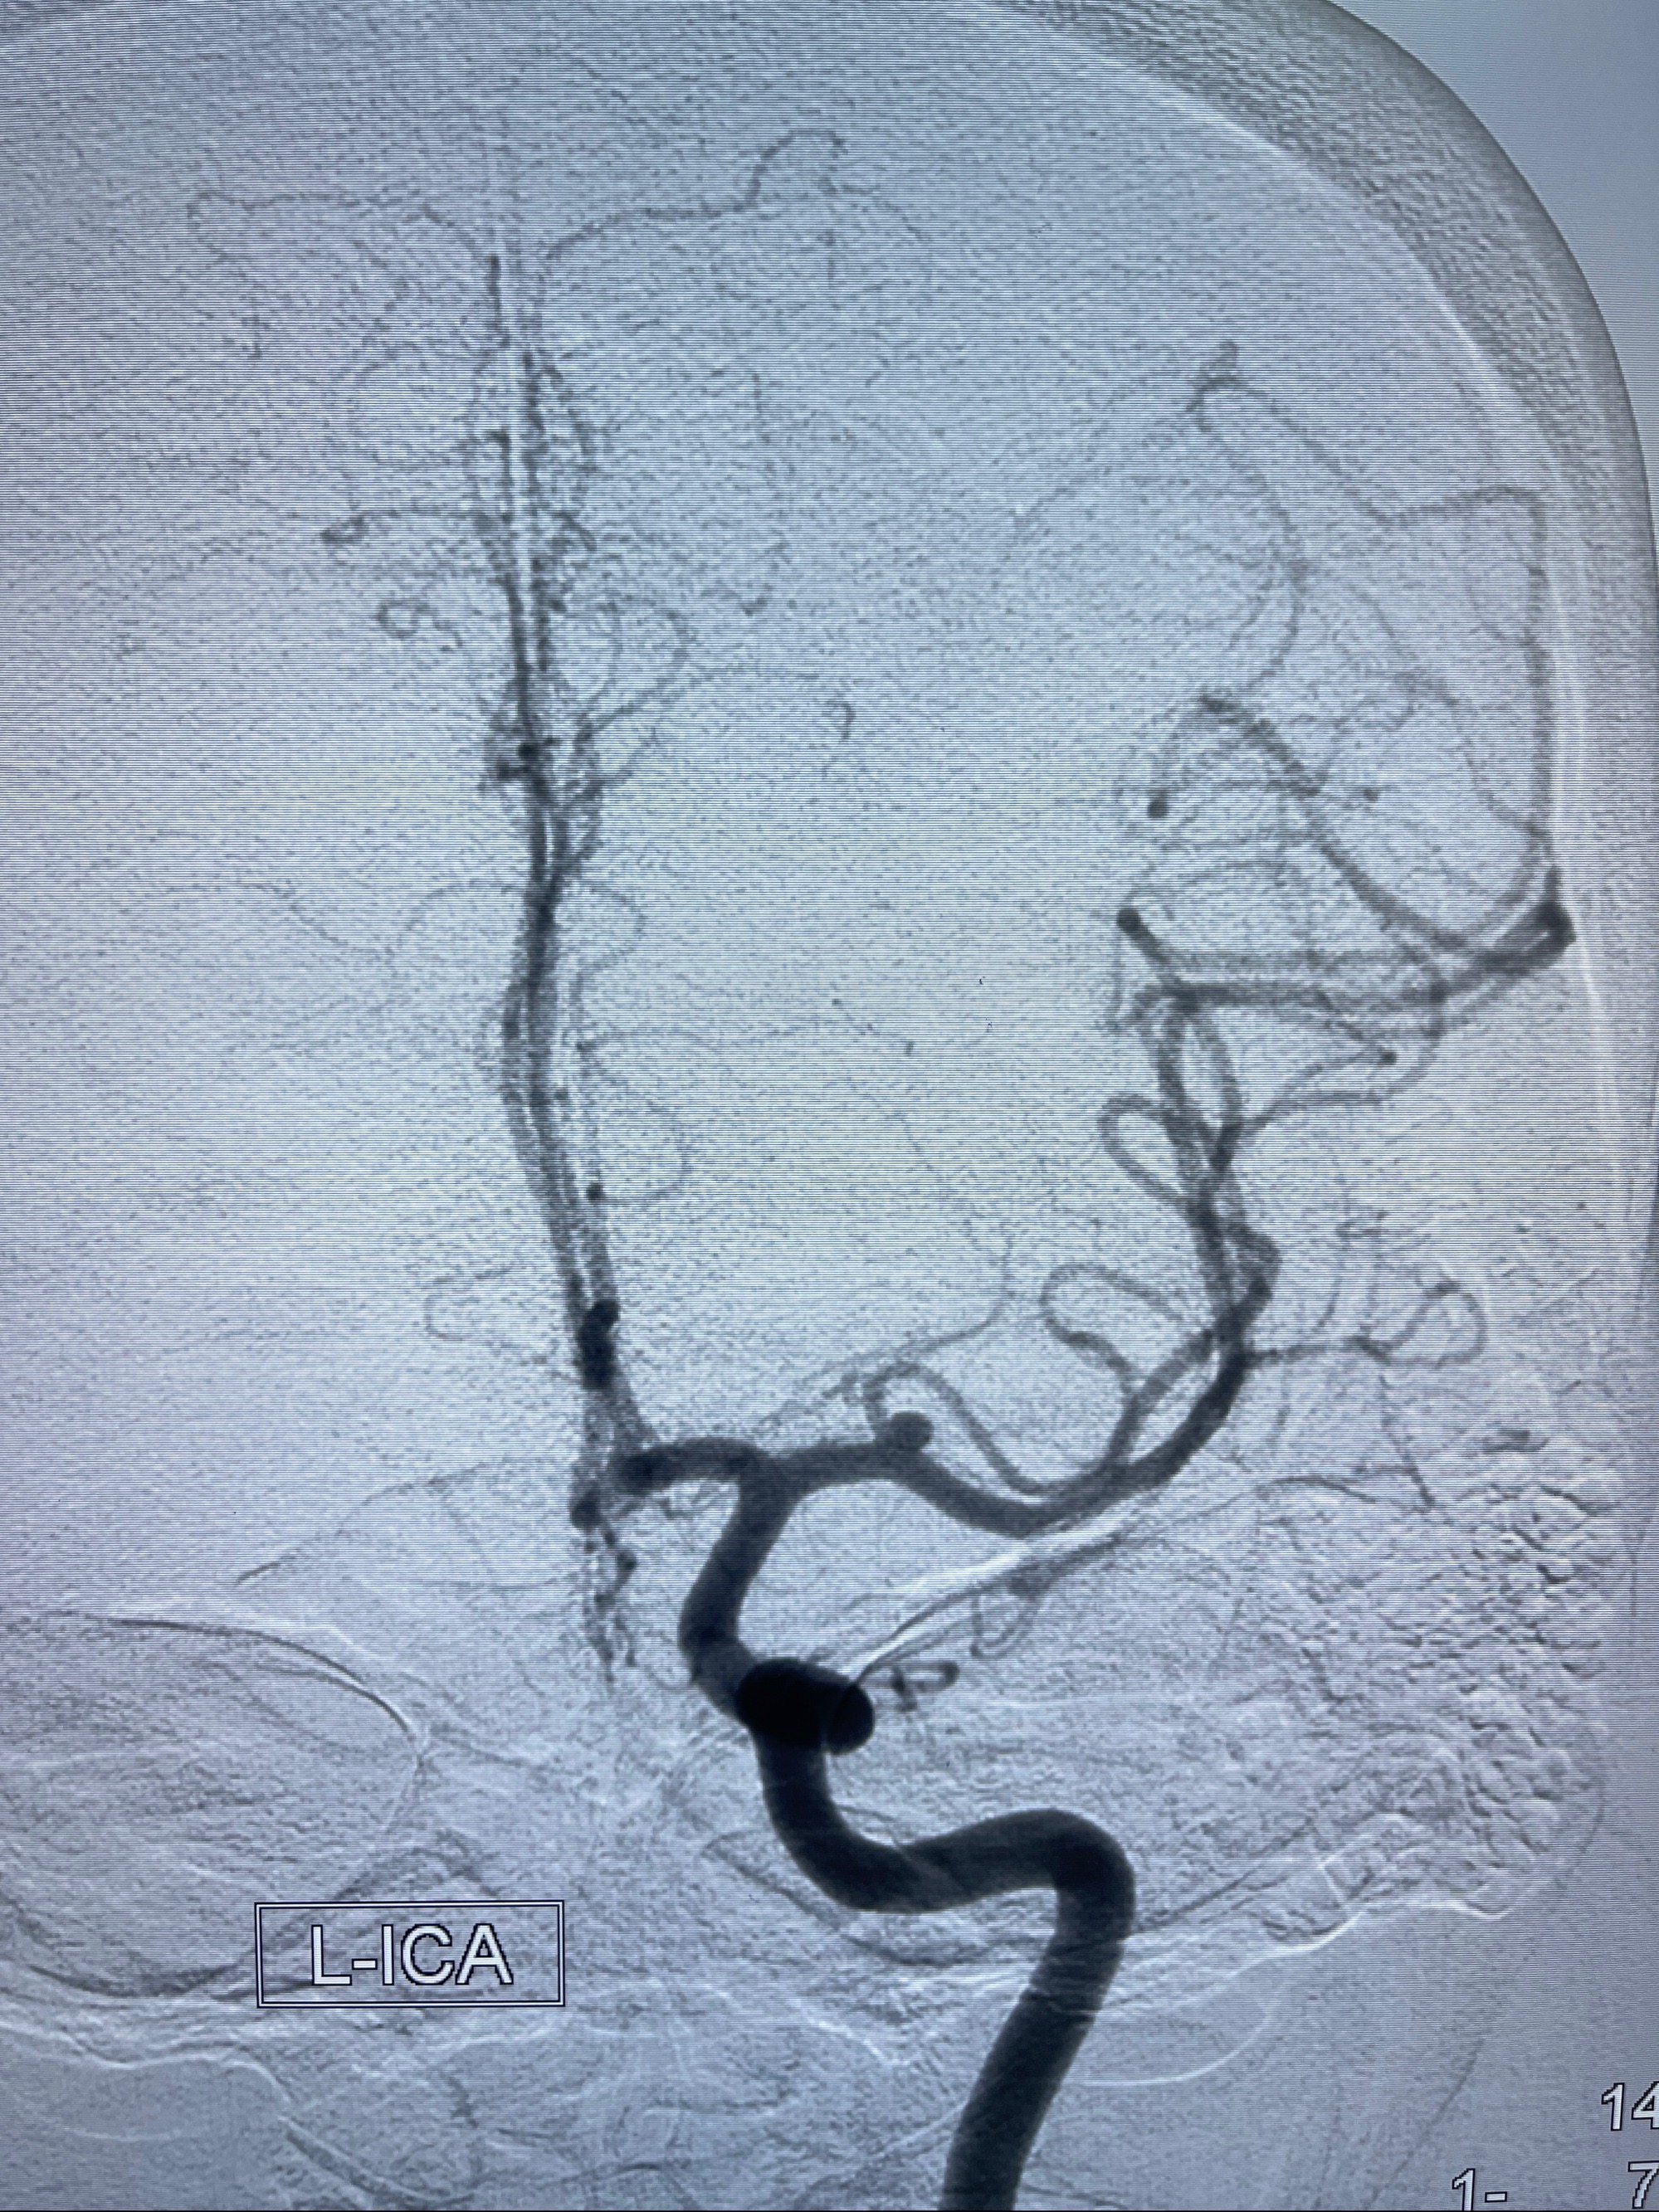

辅助检查:2023-07-12 上海大学附属第三医院 头颅CTA:左侧大脑中动脉M1段动脉瘤(1.7*3.4mm),右侧大脑前动脉A1段缺如,左侧椎动脉V4段纤细。

2023-08-14DSA:

左侧大脑中动脉动脉瘤,约2.6-2.8-3.4-2mm大小(瘤颈部、瘤体部、瘤高)

1.左侧大脑中动脉动脉瘤,约2.6-2.8-3.4-2mm大小(瘤颈部、瘤体部、瘤高)

2.外科手术夹闭or介入支架辅助栓塞